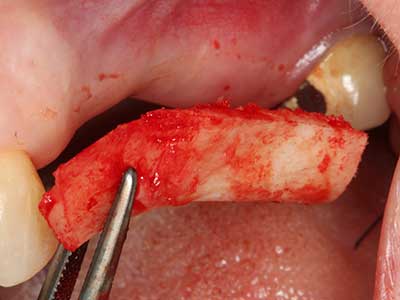

Autologous bone transplants are used in the form of blocks, shells, rings and are also combined with bone replacement materials as chips. If the implant site is prepared at the same time as the augmentation, various bone filter systems have proven effective for collecting the resulting bone chips. As an alternative, the implant site can be prepared using a low-speed device without irrigation. If an implant is not inserted, bone chips can be harvested from the periphery with bone scrapers. This is also possible with piezo surgery using specialized attachments that yield higher-quality bone chips compared chips harvested with round drills, as has been confirmed in a study comparing the two methods (Chiriac, Herten et al. 2005).

Piezo surgery has additional advantages when harvesting bone blocks. In addition to the high precision with osteotomy described above, the use of the thin saw tips specifically minimizes loss of material. Greater loss of material during harvesting can be expected with the thicker instrument tips, particularly when using Lindemann drills (Lakshmiganthan, Gokulanathan et al. 2012). The basal separation, which is necessary particularly for retromolar block transplants, is simplified by specially designed rectangular saws, with the result that piezo surgery is viewed as a precise, simple and safe procedure for harvesting retromolar bone blocks (Happe 2007) (Fig. 1-12).